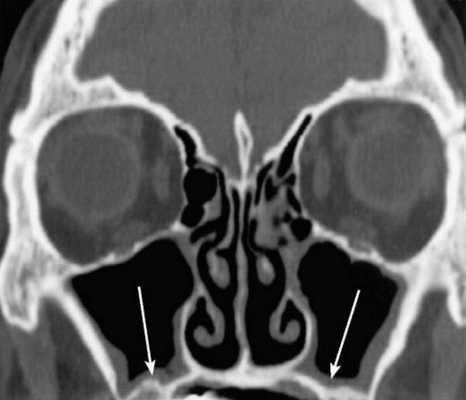

На снимке концентрическая воспалительная гипертрофия (указана стрелками) слизистой оболочки гайморовых пазух

Концентрическая воспалительная гипертрофия ячеек решетчатой кости (указана стрелками)